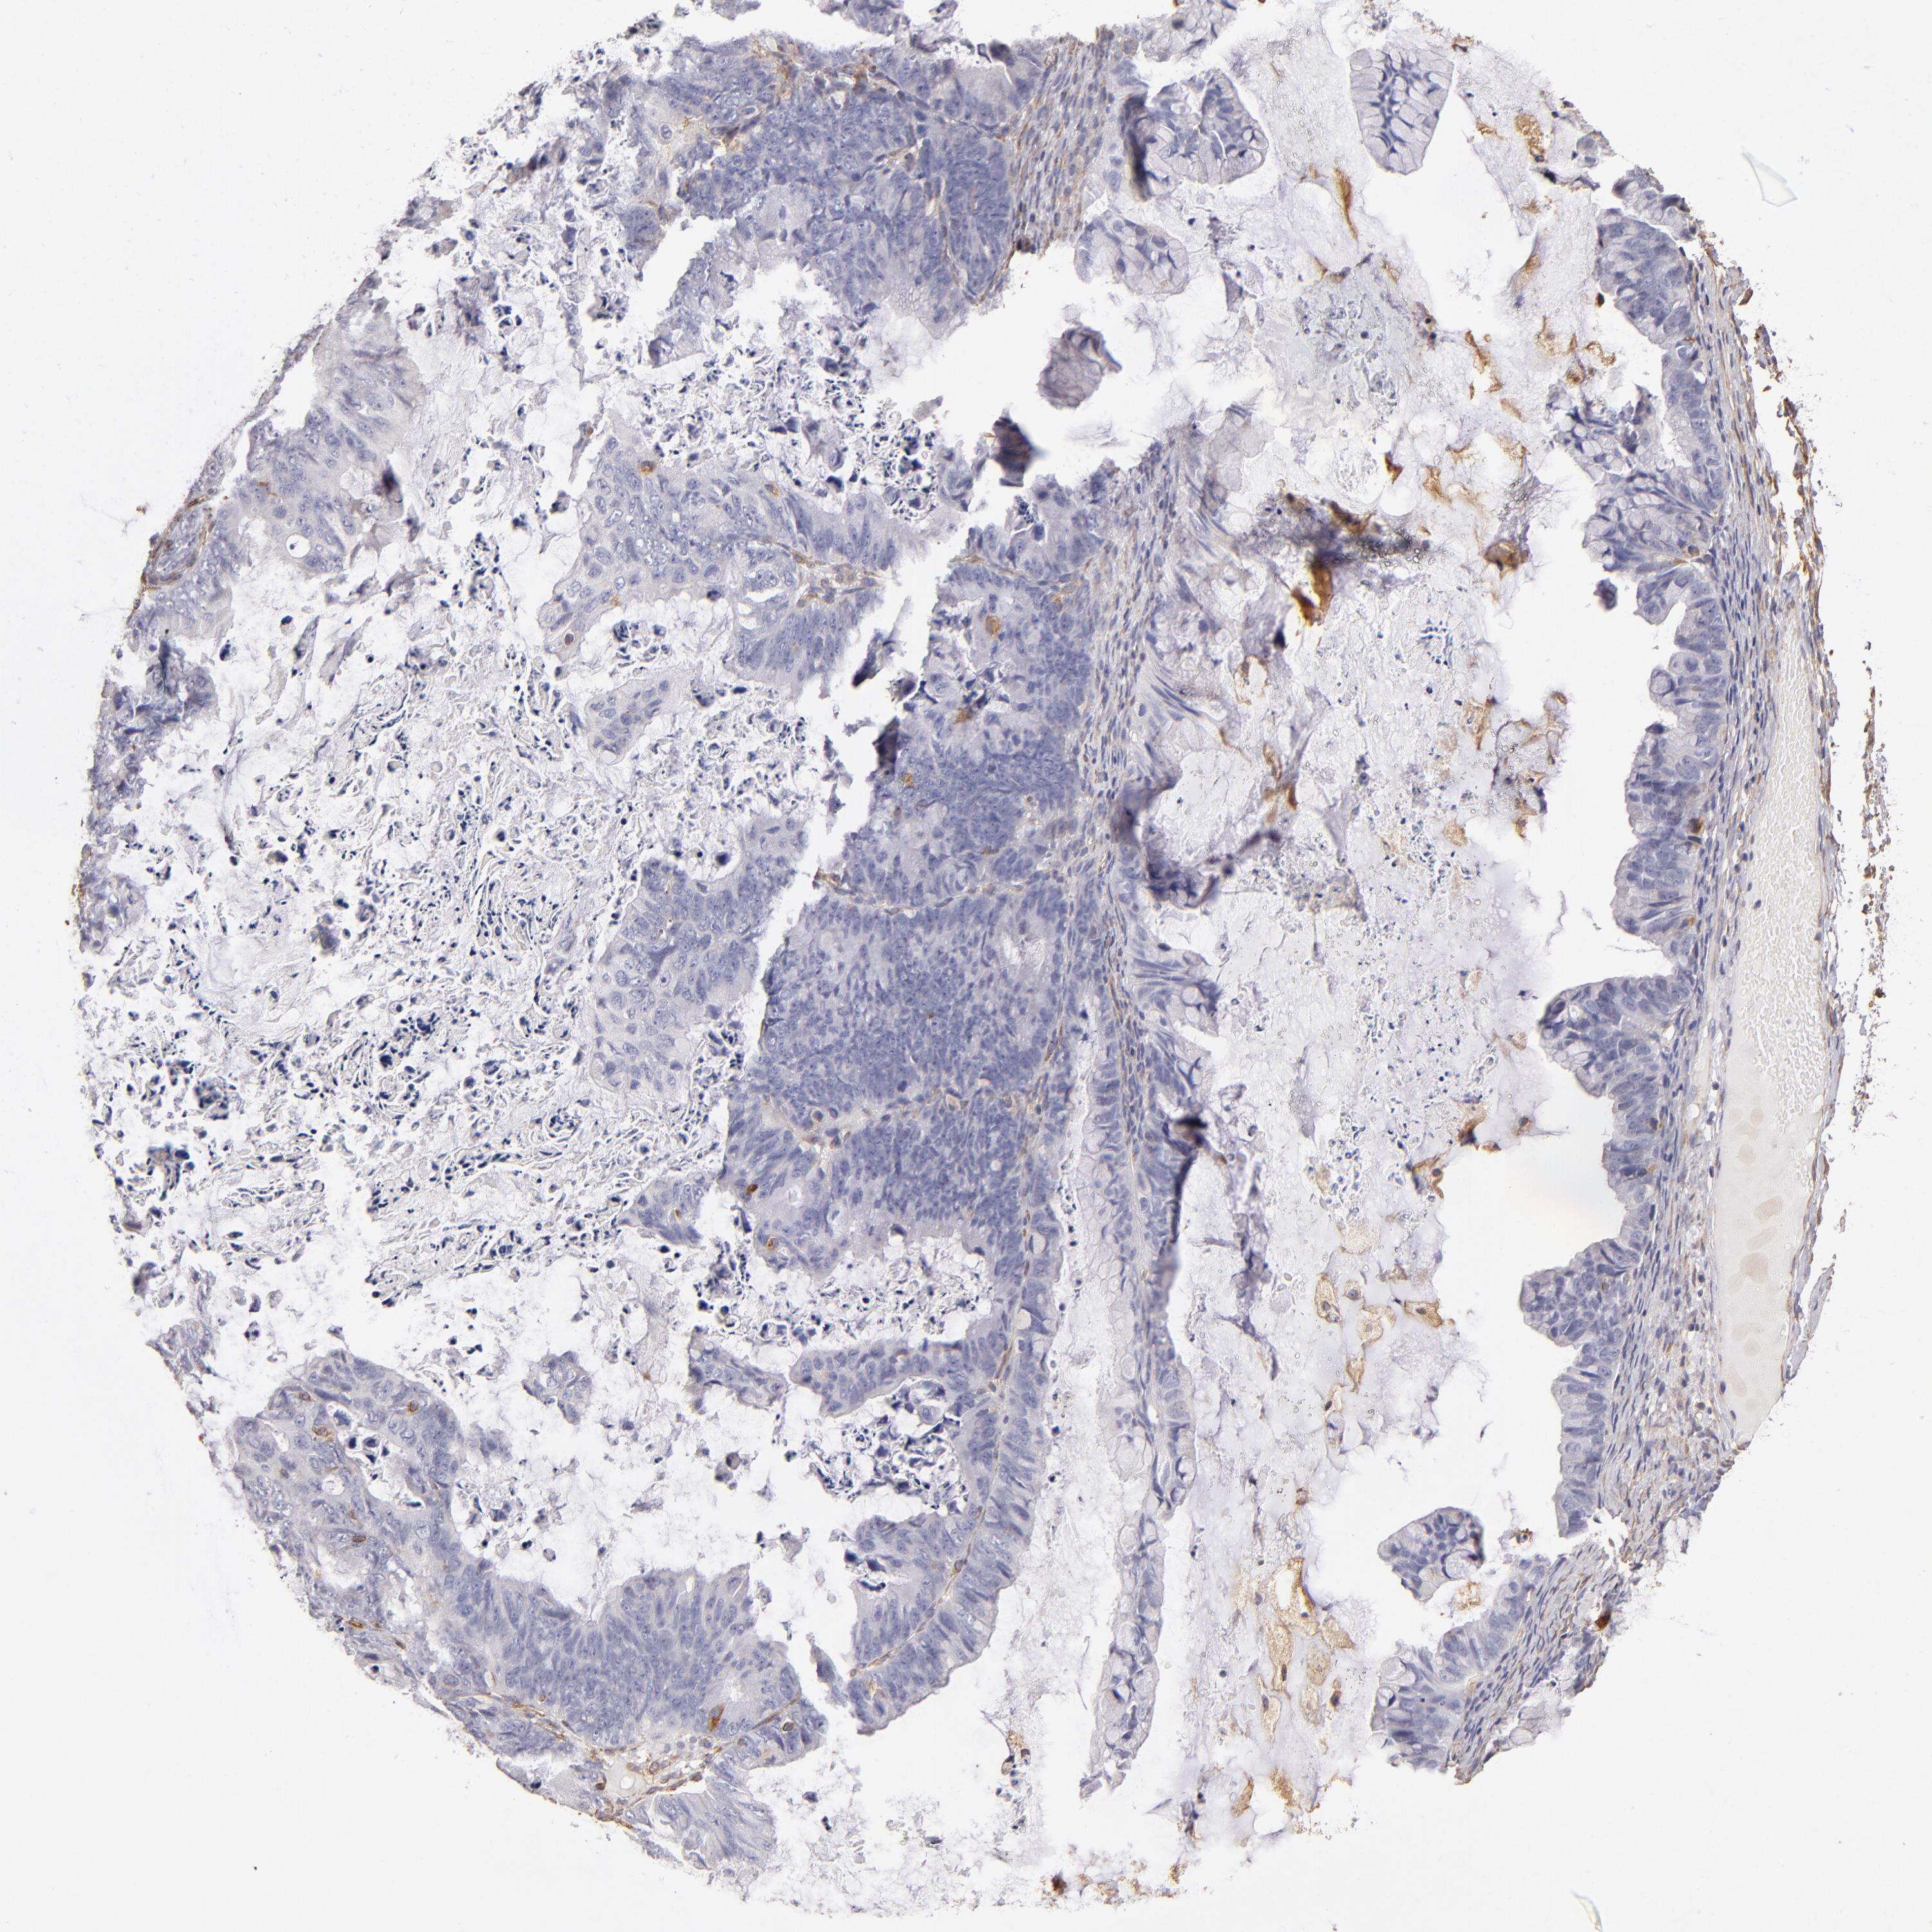

OVARIAN CANCER - Protein expressioni

A mouse-over function shows sample information and annotation data. Click on an image to view it in a full screen mode. Samples can be filtered based on level of antibody staining by selecting one or several of the following categories: high, medium, low and not detected. The assay and annotation is described here.

Note that samples used for immunohistochemistry by the Human Protein Atlas do not correspond to samples in the TCGA dataset.

Antibody stainingi

Antibody staining in the annotated cell types in the current human tissue is reported as not detected, low, medium, or high, based on conventional immunohistochemistry profiling in selected tissues. This score is based on the combination of the staining intensity and fraction of stained cells.

Each image is clickable and will lead to virtual microscopy that enables deeper exploration of all samples and also displays staining intensity scores, fraction scores and subcellular localization as well as patient and tissue information for each sample.

Antibody HPA002380

Staining

High

Medium

Low

Not detected

Intensity

Strong

Moderate

Weak

Negative

Quantity

>75%

75%-25%

<25%

None

Location

Nuclear

Cytoplasmic/membranous

Cytoplasmic/membranous,nuclear

Cystadenocarcinoma, serous, NOS

Cystadenocarcinoma, mucinous, NOS

Carcinoma, endometroid